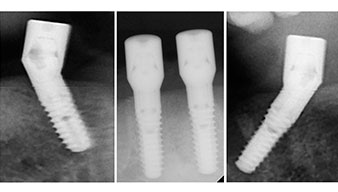

È stata eseguita una tomografia computerizzata Dentale Cone Beam in 3D (CBCT, con Planmeca) per aiutare la programmazione dell'intervento e la riduzione di rischi. L'esame ha evidenziato che la qualità e quantità dell'osso disponibile era sufficiente per eseguire l'intervento e la ricostruzione immediata, utilizzando il metodo Fast & Fixed. In base al protocollo del sistema, gli impianti sono stati inseriti in posizione 35, 32, 42 e 45. Gli impianti distali vengono installati a un angolo massimo di 45 gradi. Così facendo, il profilo che ne risulta viene spostato in posizione posteriore, generando un poligono di supporto più ampio (Fig. 3).

È stato avvitato un moncone angolato di 35 gradi per compensare la divergenza degli impianti distali. Ne risulta un profilo globale degli impianti situato il più perpendicolare possibile al piano occlusale. Questa situazione è un prerequisito per il posizionamento occlusale di protesi provvisorie e, successivamente, di quelle definitive (Fig. 15 e 16).